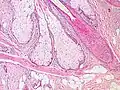

Sebaceous glands are found in hair-covered areas, where they are connected to hair follicles. One or more glands may surround each hair follicle, and the glands themselves are surrounded by arrector pili muscles, forming a pilosebaceous unit. The glands have an acinar structure (like a many-lobed berry), in which multiple glands branch off a central duct. The glands deposit sebum on the hairs and bring it to the skin surface along the hair shaft. The structure, consisting of hair, hair follicles, arrector pili muscles, and sebaceous glands, is an epidermal invagination known as a pilosebaceous unit.[4]

Relative to keratinocytes that make up the hair follicle, sebaceous glands are composed of huge cells (sebocytes) with many large vesicles that contain the sebum.[8] These cells express Na+ and Cl− ion channels, ENaC and CFTR (see Fig. 6 and Fig. 7 in reference[8]).